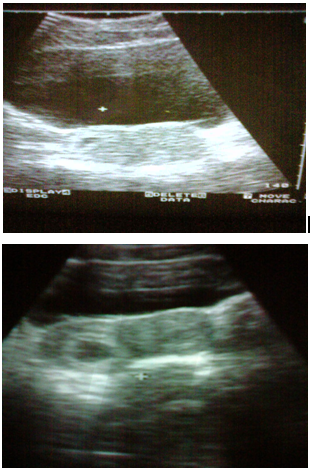

Figure 3 Patient G.J. 1988 age Ultrasound examination carried out 6 times. Spontaneously delivered a live male child 2600/50.